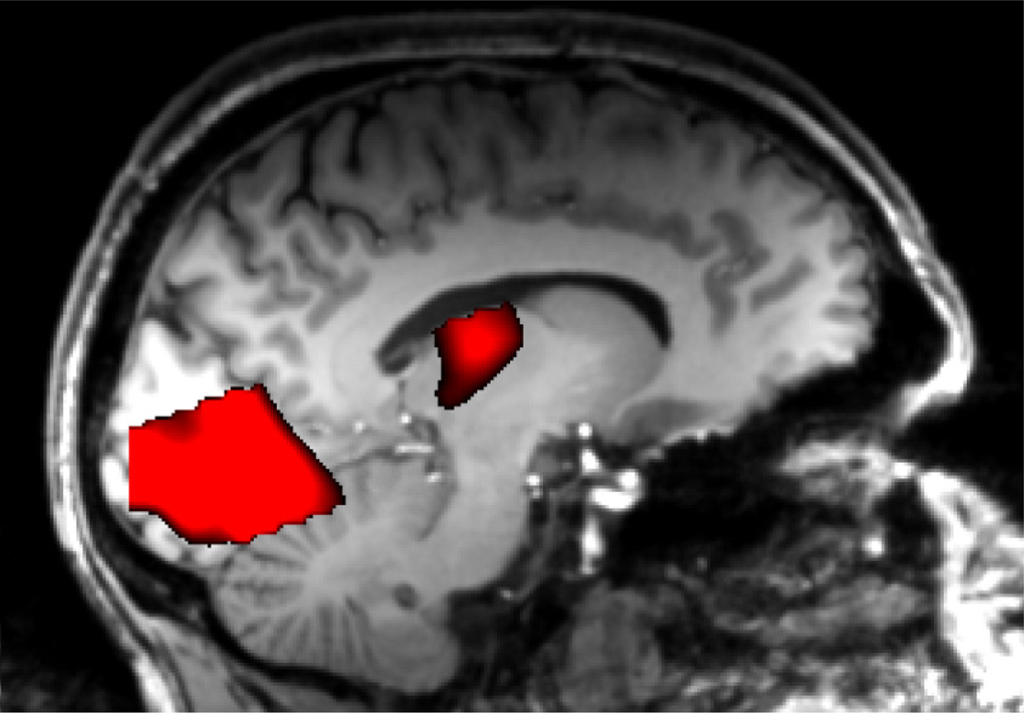

2.2. Functional MRI

2.3. Multi-Modal Integration of MRI, fMRI, and Slow Cortical Potentials (SCP, DC-EEG)

Functional brain imaging: